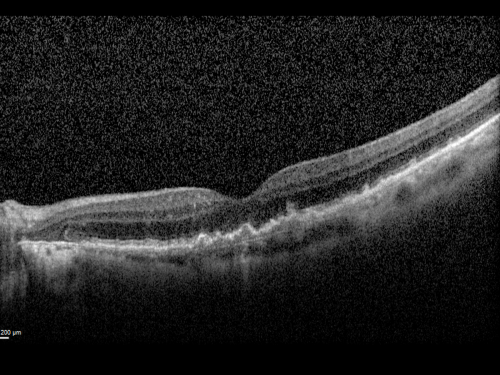

Reticular Macular Disease (Pseudo-drusen) Both Eyes - Wet AMD OS - Dry AMD OD SD-OCT

84-year-old woman has wet age-related macular degeneration in the left eye and dry macular degeneration in the right eye.  She takes the eye vitamins and her vision is stable since she was treated three months ago with Avastin.   OD 20/50,  OS 20/32